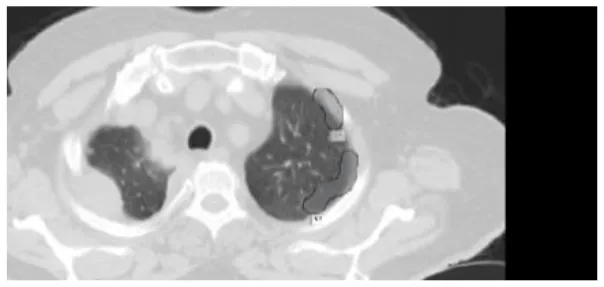

The results were enhanced by using the ROI segmentation method. It seems that it has the capacity to address the problem of the model's inaccurate positioning of labels. As a consequence, following the recommended methodology may lead to decreased losses. Furthermore, it was shown that the training session continued to slow down. The lesson is enhanced in its effectiveness as shown in Figure 8. It is advisable to apply the same treatment to both one-dimensional and two-dimensional data. The objective of this strategy is to eliminate any errors in labeling in both directions. Over time, there was a gradual reduction in the size of each point. Engaging in conversations with individuals helps achieve both objectives.

Figure 8

Prior to and during the segmentation procedure, the ground-truth forecast was used in each of these instances.

If the dataset is insufficient, it may be necessary to round up more labels. Overall, there were 159 cancerous tumors, and the standard deviation of the Dice coefficient was 0.2. Although its model had a low mFPI, the DL-based model was successful in detecting lung tumors from chest X-rays, the results are shown in Figure 8. The evaluations of the proposed models are presented in Table 8.